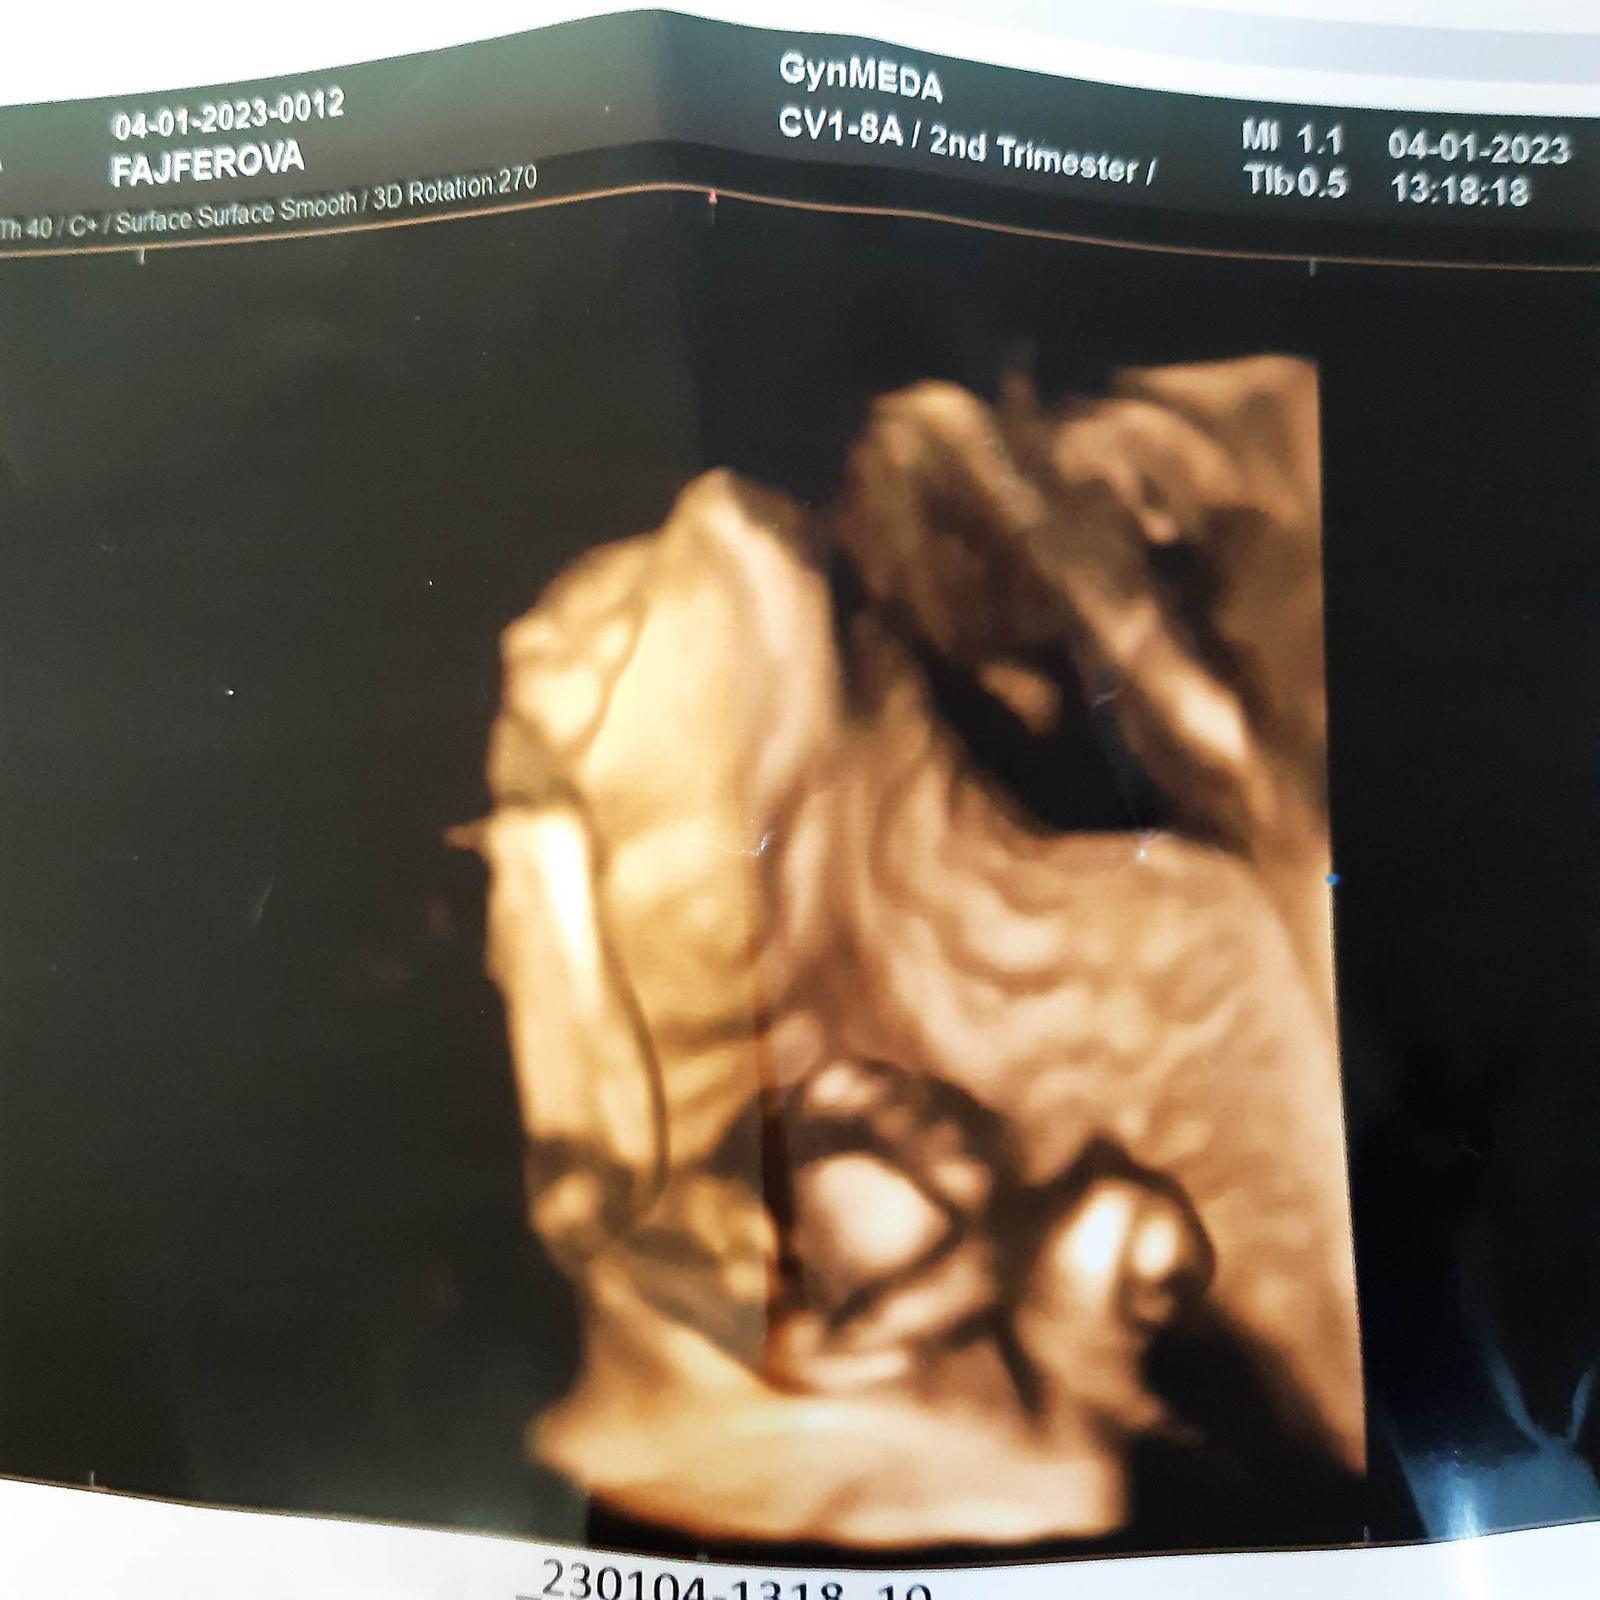

Tak holky dnes 2. trimestralni screening a vse v poradku 🙂 <3